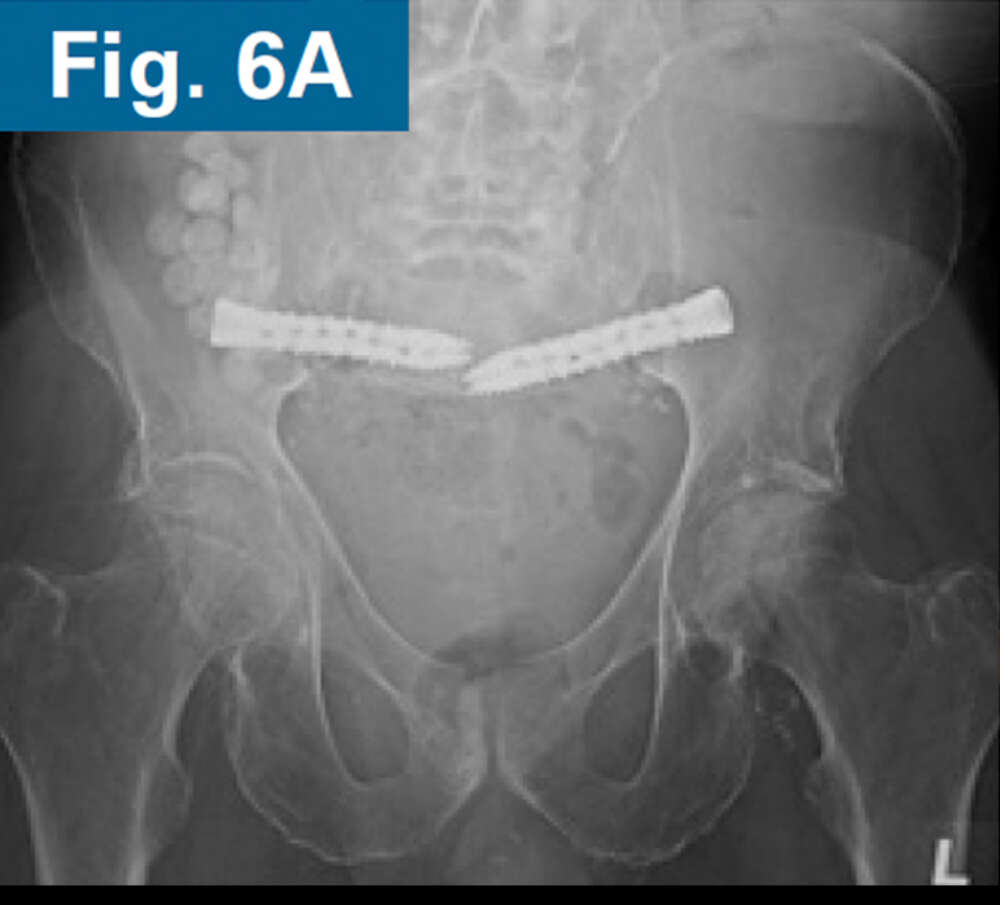

• Immediate postoperative CT scan demonstrate safe placement of implants (Figs. 5A and 5B).

• AP and standing lateral sacral view at 3 months follow-up.

• Callous formation noted on the lateral radiograph (Figs. 6A and 6B).

• Clinically, the patient is ambulating comfortably and is not requiring opioids.4